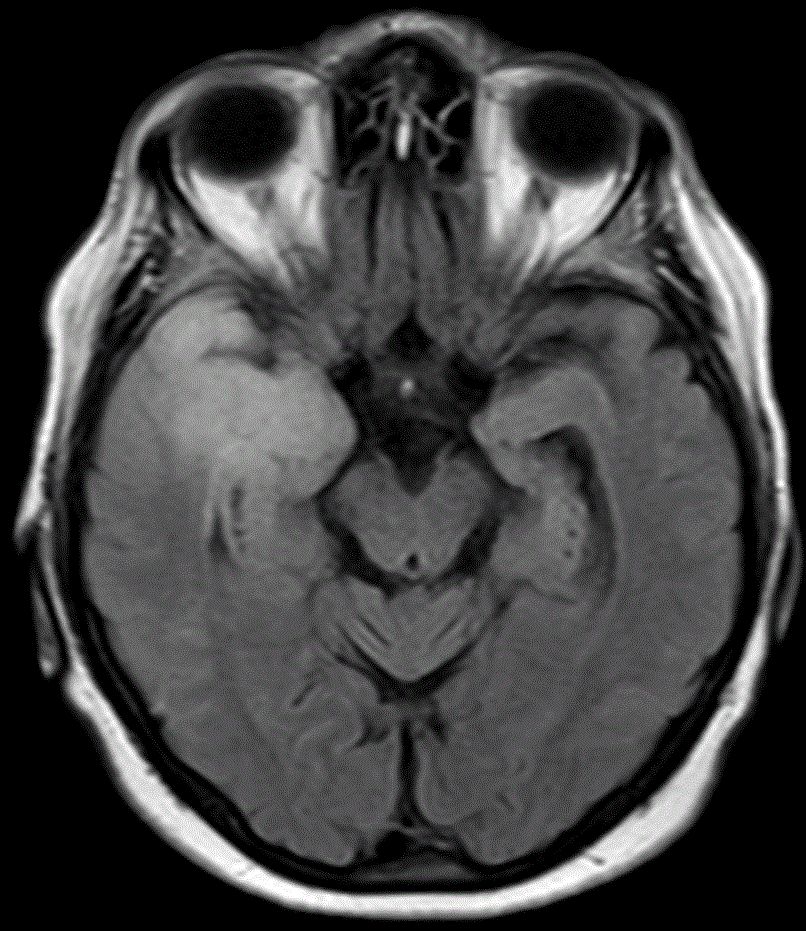

CT |

51-jähriger Mann mit Sehstörung rechts, Kopfschmerz und Schwindel.

Das CT zeigt einen Herd im Splenium corporis callosi links.

Der Tumor erreicht das Hinterhorn.

Stereotaktiosche Punktion: Glioblastoma multiforme.

Eine 2. Läsion im Inselbereich wurde nicht histologisch gesichert.![]() | ||||